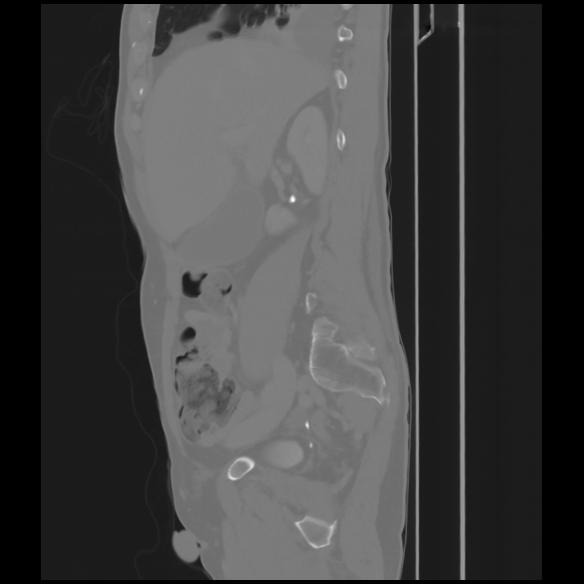

7 CUERPO,CE,Sagittal,3.000,CUERPO,Sagittal,